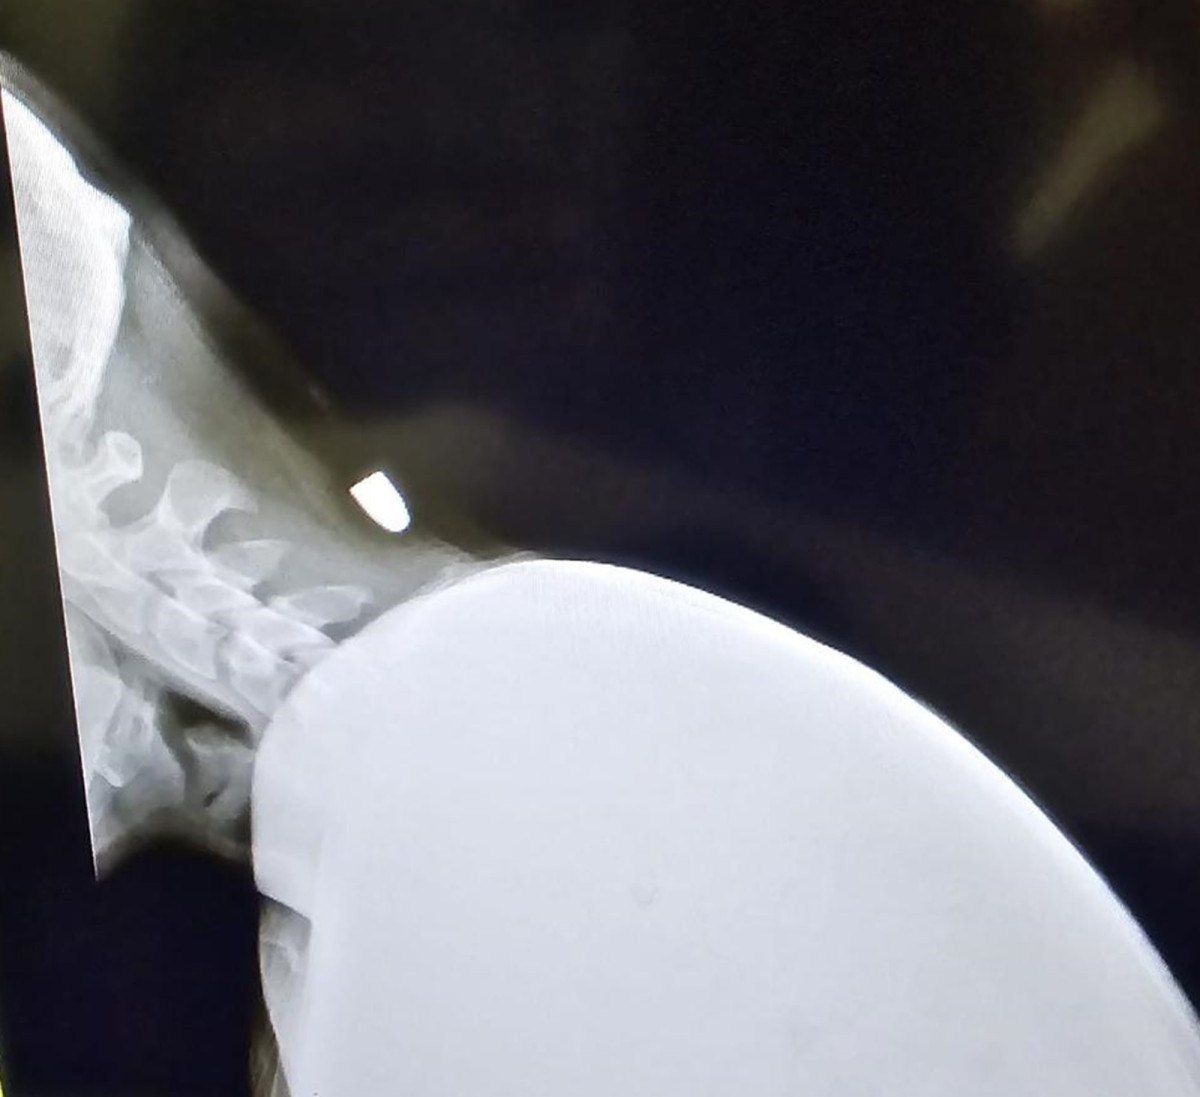

Geçen Pazartesi günü ameliyat olan Yavuz’un ensesindeki mermi 40 dakikalık ameliyatla çıkarıldı.

Arkadaşlarıyla otururken yorgun merminin isabet ettiğini dile getiren Yunus Emre Yavuz, “İşte çalışıyorduk ve mola verdik. Akşam 19:30 sularında otururken biraz eğildim. Eğildiğim anda merminin düşmesi bir oldu. Biri sanki sertçe sopayla vurmuş gibi hissettim. Arkadaşlar yaraya baktığında kurşun olduğunu gördüler. Hastaneye götürdüler. Röntgen ve filmlere bakıldığında mermi olduğu anlaşıldı.

Hastane sürecinde; röntgen ve MR filmleri çekildikten sonra ameliyat olmalısın dediler. Geçen pazartesi ameliyata girdim ve 40 dakika sürdü. Şükürler olsun sağlam çıktım. Kurşunu da incelenmesi için Adana’ya gönderildi. Zorlu bir süreç oldu ama atlattık” dedi.

“ŞAH DAMARIMIN 2 SANTİM YANINA İSABET ETTİ”

Merminin şah damarının 2 santimetre yakınına isabet ettiğini Yavuz, “Ölümden döndüm. Ben değil başkası da olabilirdi veya ölebilirdim. Ben ölmedim ama başkasının başına gelip ölebilirdi. Kurşun şah damarının 2 cm yanındaydı ve biraz daha derine inseydi felç kalacaktım veya morgda olacaktım.